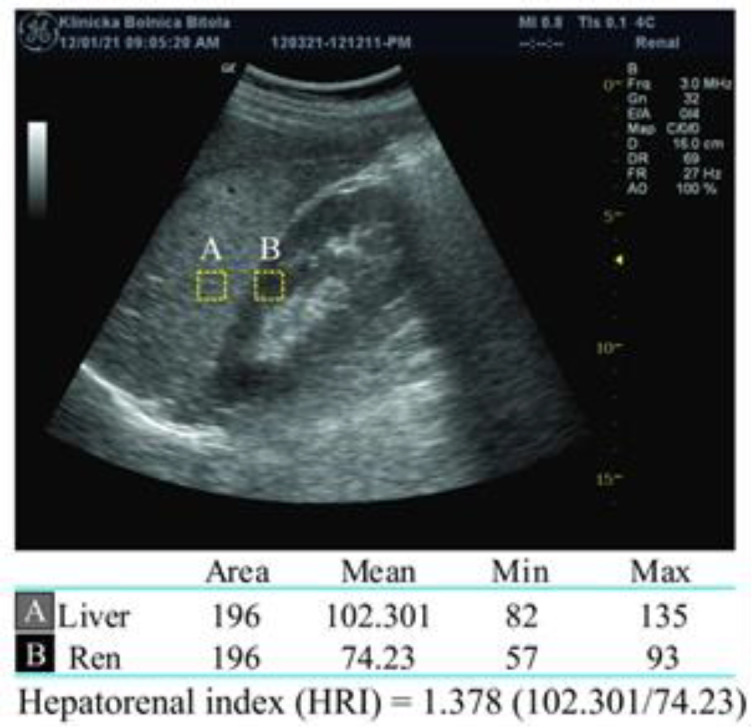

Methods: LFT, glucose, and lipid tests were determined in 168 NAFLD patients, at baseline and after three-month drug treatment. HRI was calculated by Image J software analyzing the ultrasound images, and according its value, 3 groups of NAFLD were formed.

Results: The HRI at baseline (1.3598±0.1744) and after 3 months therapy (1.3061±0.1923) differs significantly (p<0.0001). Plasma glucose (FPG) (p<0.0001), glycated hemoglobin (HbA1c) (P=0.002), alanine aminotransferase (ALT) (p<0.0001), aspartate aminotransferase (AST) (P=0.0006), gamma-glutamil transferase (γ-GT) (P=0.0053), high density lipoprotein cholesterol (HDL-Ch) (p<0.0001) and triglycerides (P=0.041) differ significantly, too. HRI is positively correlated with: HbA1c (P=0.035), ALT (P=0.002), AST (P=0.003), γ-GT (P=0.043), and triglycerides (P=0.002) and inversely correlated with HDL-Ch (P=0.011). In multiple regression results (standard coefficient and p-value), the independent predictors for HRI in NAFLD patients were: HbA1c (0.1443, 0.0004), ALT (0.001142, 0.0081), triglycerides (0.0431, 0.0235) and γ-GT (0.001376, 0.0329).